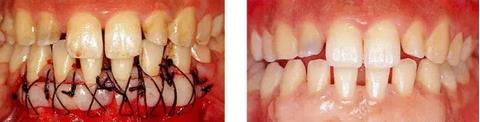

圖17-1(左) 刷牙時牙齦疼痛為主訴的17歲女性患者的初診正面照片。牙齦炎癥嚴重,下頜前牙區(qū)黏膜能看到很多血管。

圖17-2(右) 初期治療結束后的正面照片。牙齦炎癥減輕了,但牙齦還是非常脆弱,所以菌斑難以控制。